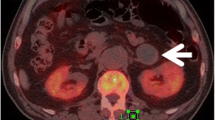

This retrospective study enrolled 178 patients with cancer history from three medical centres categorised as those with adrenal lipid-poor benign lesions or metastases. Patients were divided into training, validation, and external testing cohorts. Radiomics features were extracted from triphasic CT images (unenhanced, arterial, and venous) to establish three single-phase models and one triphasic radiomics model using logistic regression. Unenhanced and triphasic nomograms were established by incorporating significant clinico-radiological factors and radscores. The models were evaluated by the receiver operating characteristic curve, Delong’s test, calibration curve, and decision curve.

Boland GW, Dwamena BA, Jagtiani Sangwaiya M et al (2011) Characterization of adrenal masses by using FDG PET: a systematic review and meta-analysis of diagnostic test performance. Radiology. https://doi.org/10.1148/radiol.11100569/